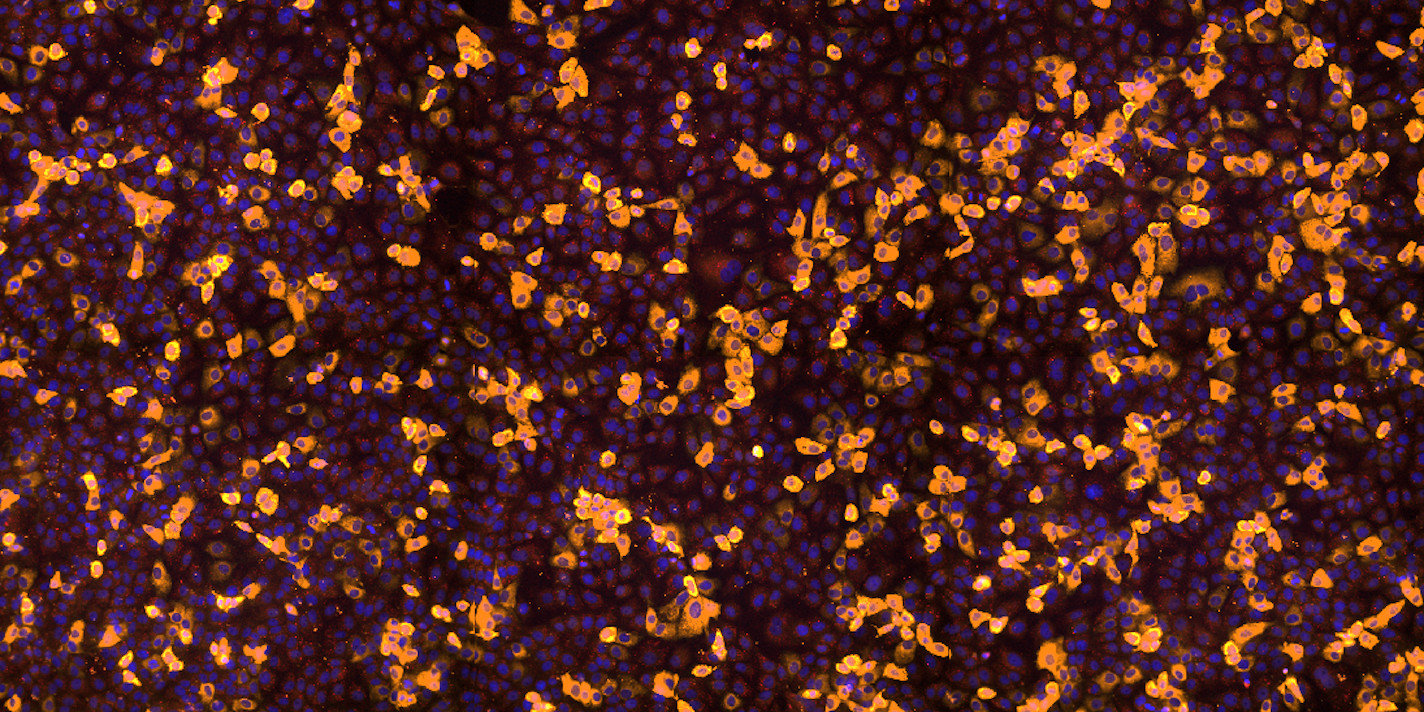

2 Detection and segmentation

BIAS supports a wide range of microscope image formats, including brightfield, fluorescent, and pathological images, either directly or through a converter application.

- Cell and object detection/segmentation – Identifying and segmenting structures within images.

- Phenotype classification – Using supervised or unsupervised machine learning algorithms.

BIAS supports both classical segmentation methods (f.x. auto-thresholding) and modern deep-learning-based models based cellular or subcellular structure segmentation models.

- Our generic models can handle a wide range of imaging modalities.

- We also offer specialized models tailored for specific tasks.

For phenotype classification, BIAS provides an interactively trainable system that supports both feature-based and image-based algorithms. Users can customize classification models to fit the specific needs of their project.